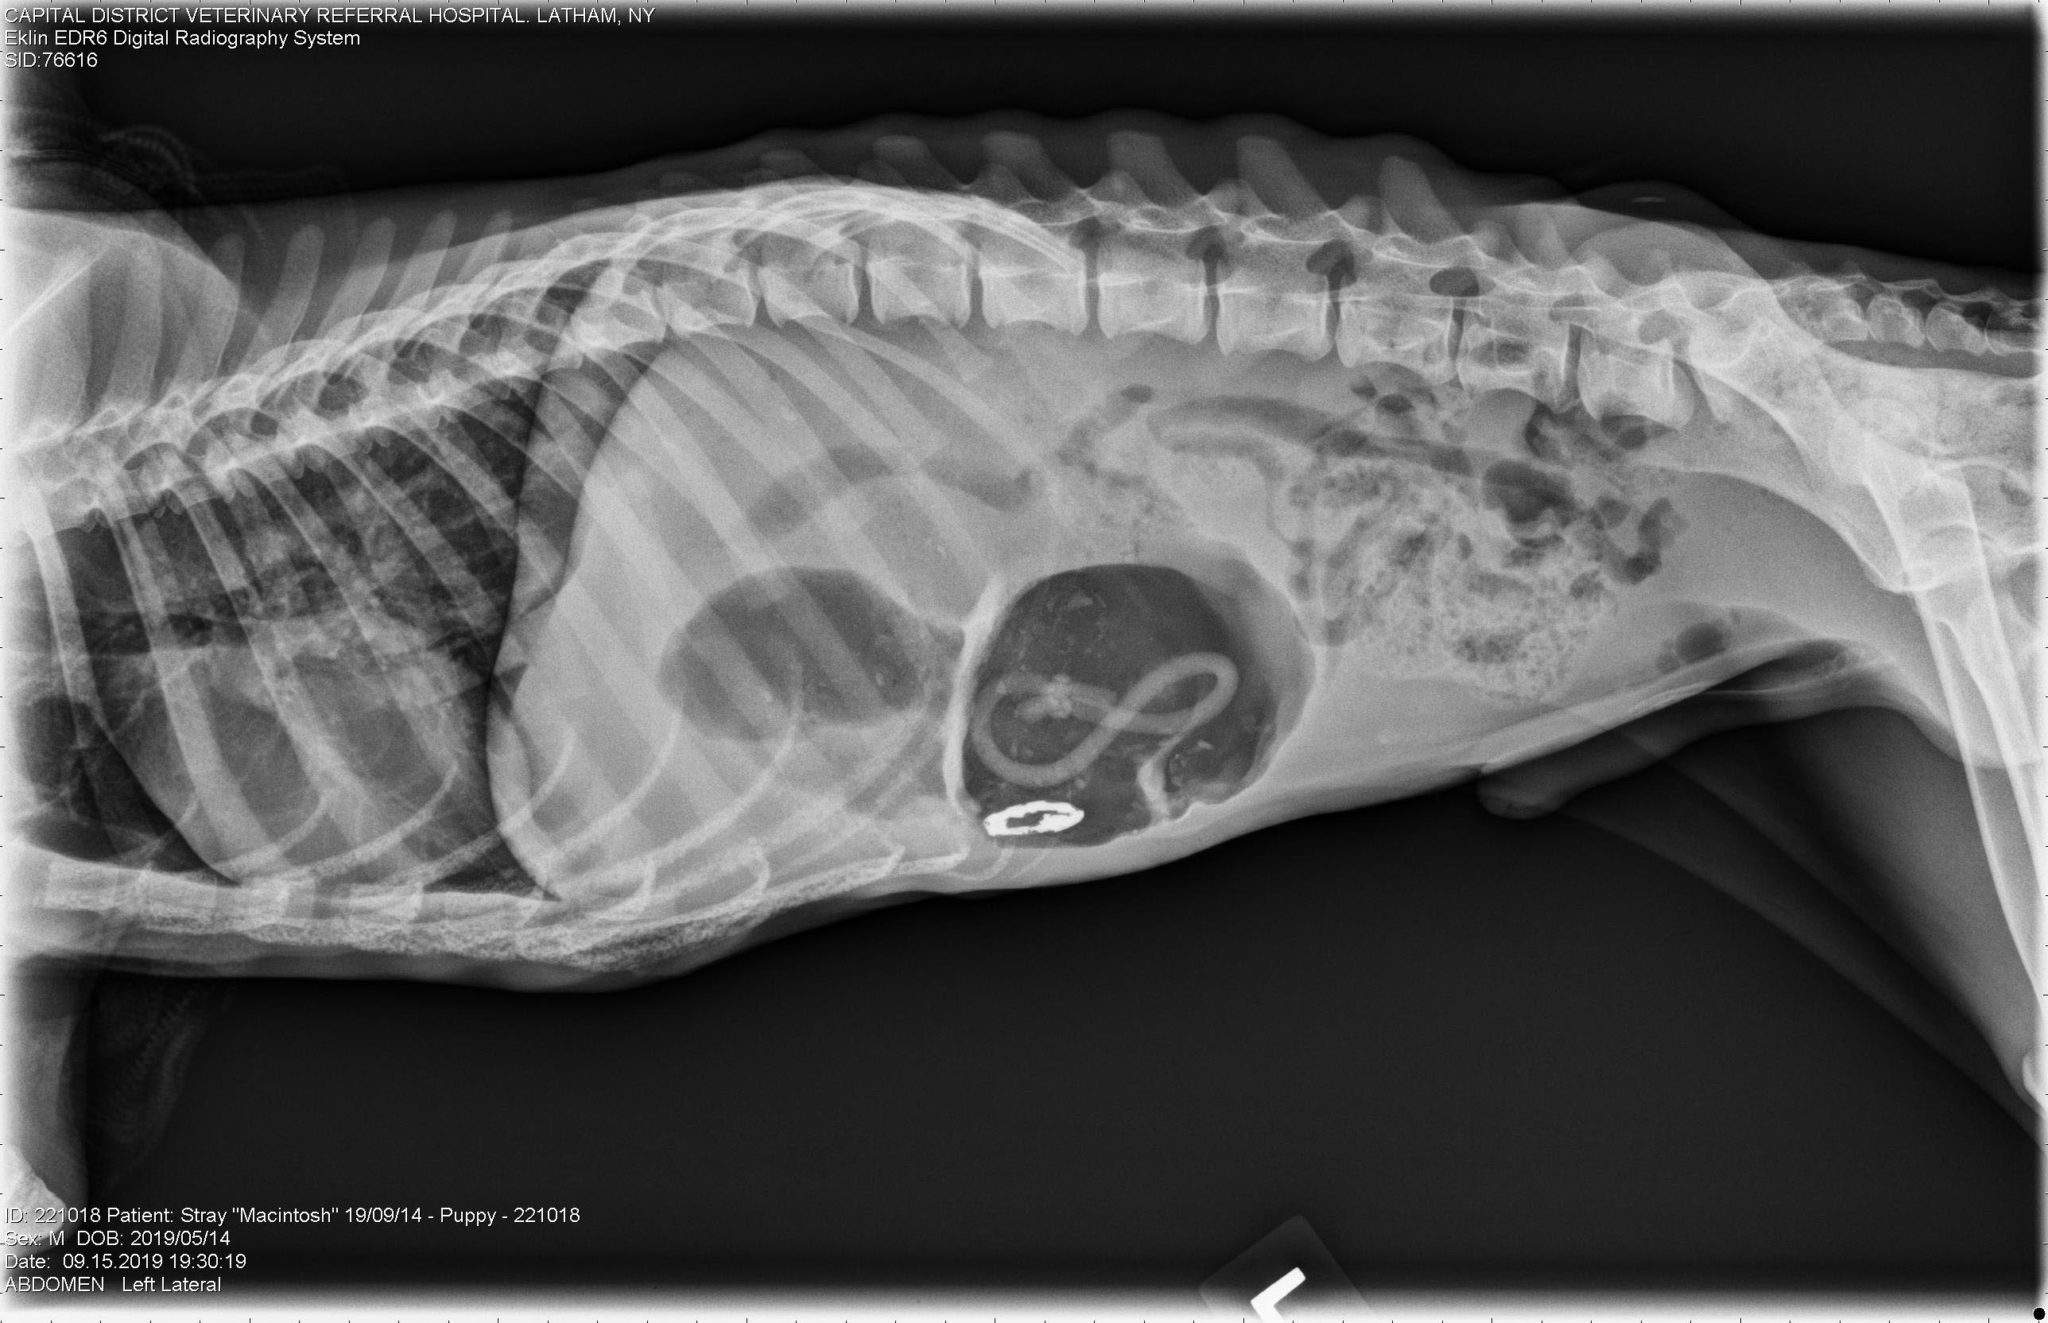

Delayed Zinc Toxicosis in a Starved Dog Ethos Veterinary Health Can Zinc Kill A Dog acute zinc poisoning is a relatively common source of poisoning in dogs. However, with prompt treatment, most dogs will recover entirely from zinc poisoning. Zinc toxicity has been seen in a wide. Most pets with zinc poisoning will develop vomiting, diarrhea, depression,. zinc causes irritation of the gastrointestinal tract. — items that contain zinc can be especially. Can Zinc Kill A Dog.

Delayed Zinc Toxicosis in a Starved Dog Can Zinc Kill A Dog If this happens, your dog's prognosis becomes poor. acute zinc poisoning is a relatively common source of poisoning in dogs. — zinc is essential for many bodily functions in dogs, but when ingested in large amounts, it can lead to toxic. When canines ingest certain types of zinc, there is a. zinc is an essential trace metal. Can Zinc Kill A Dog.